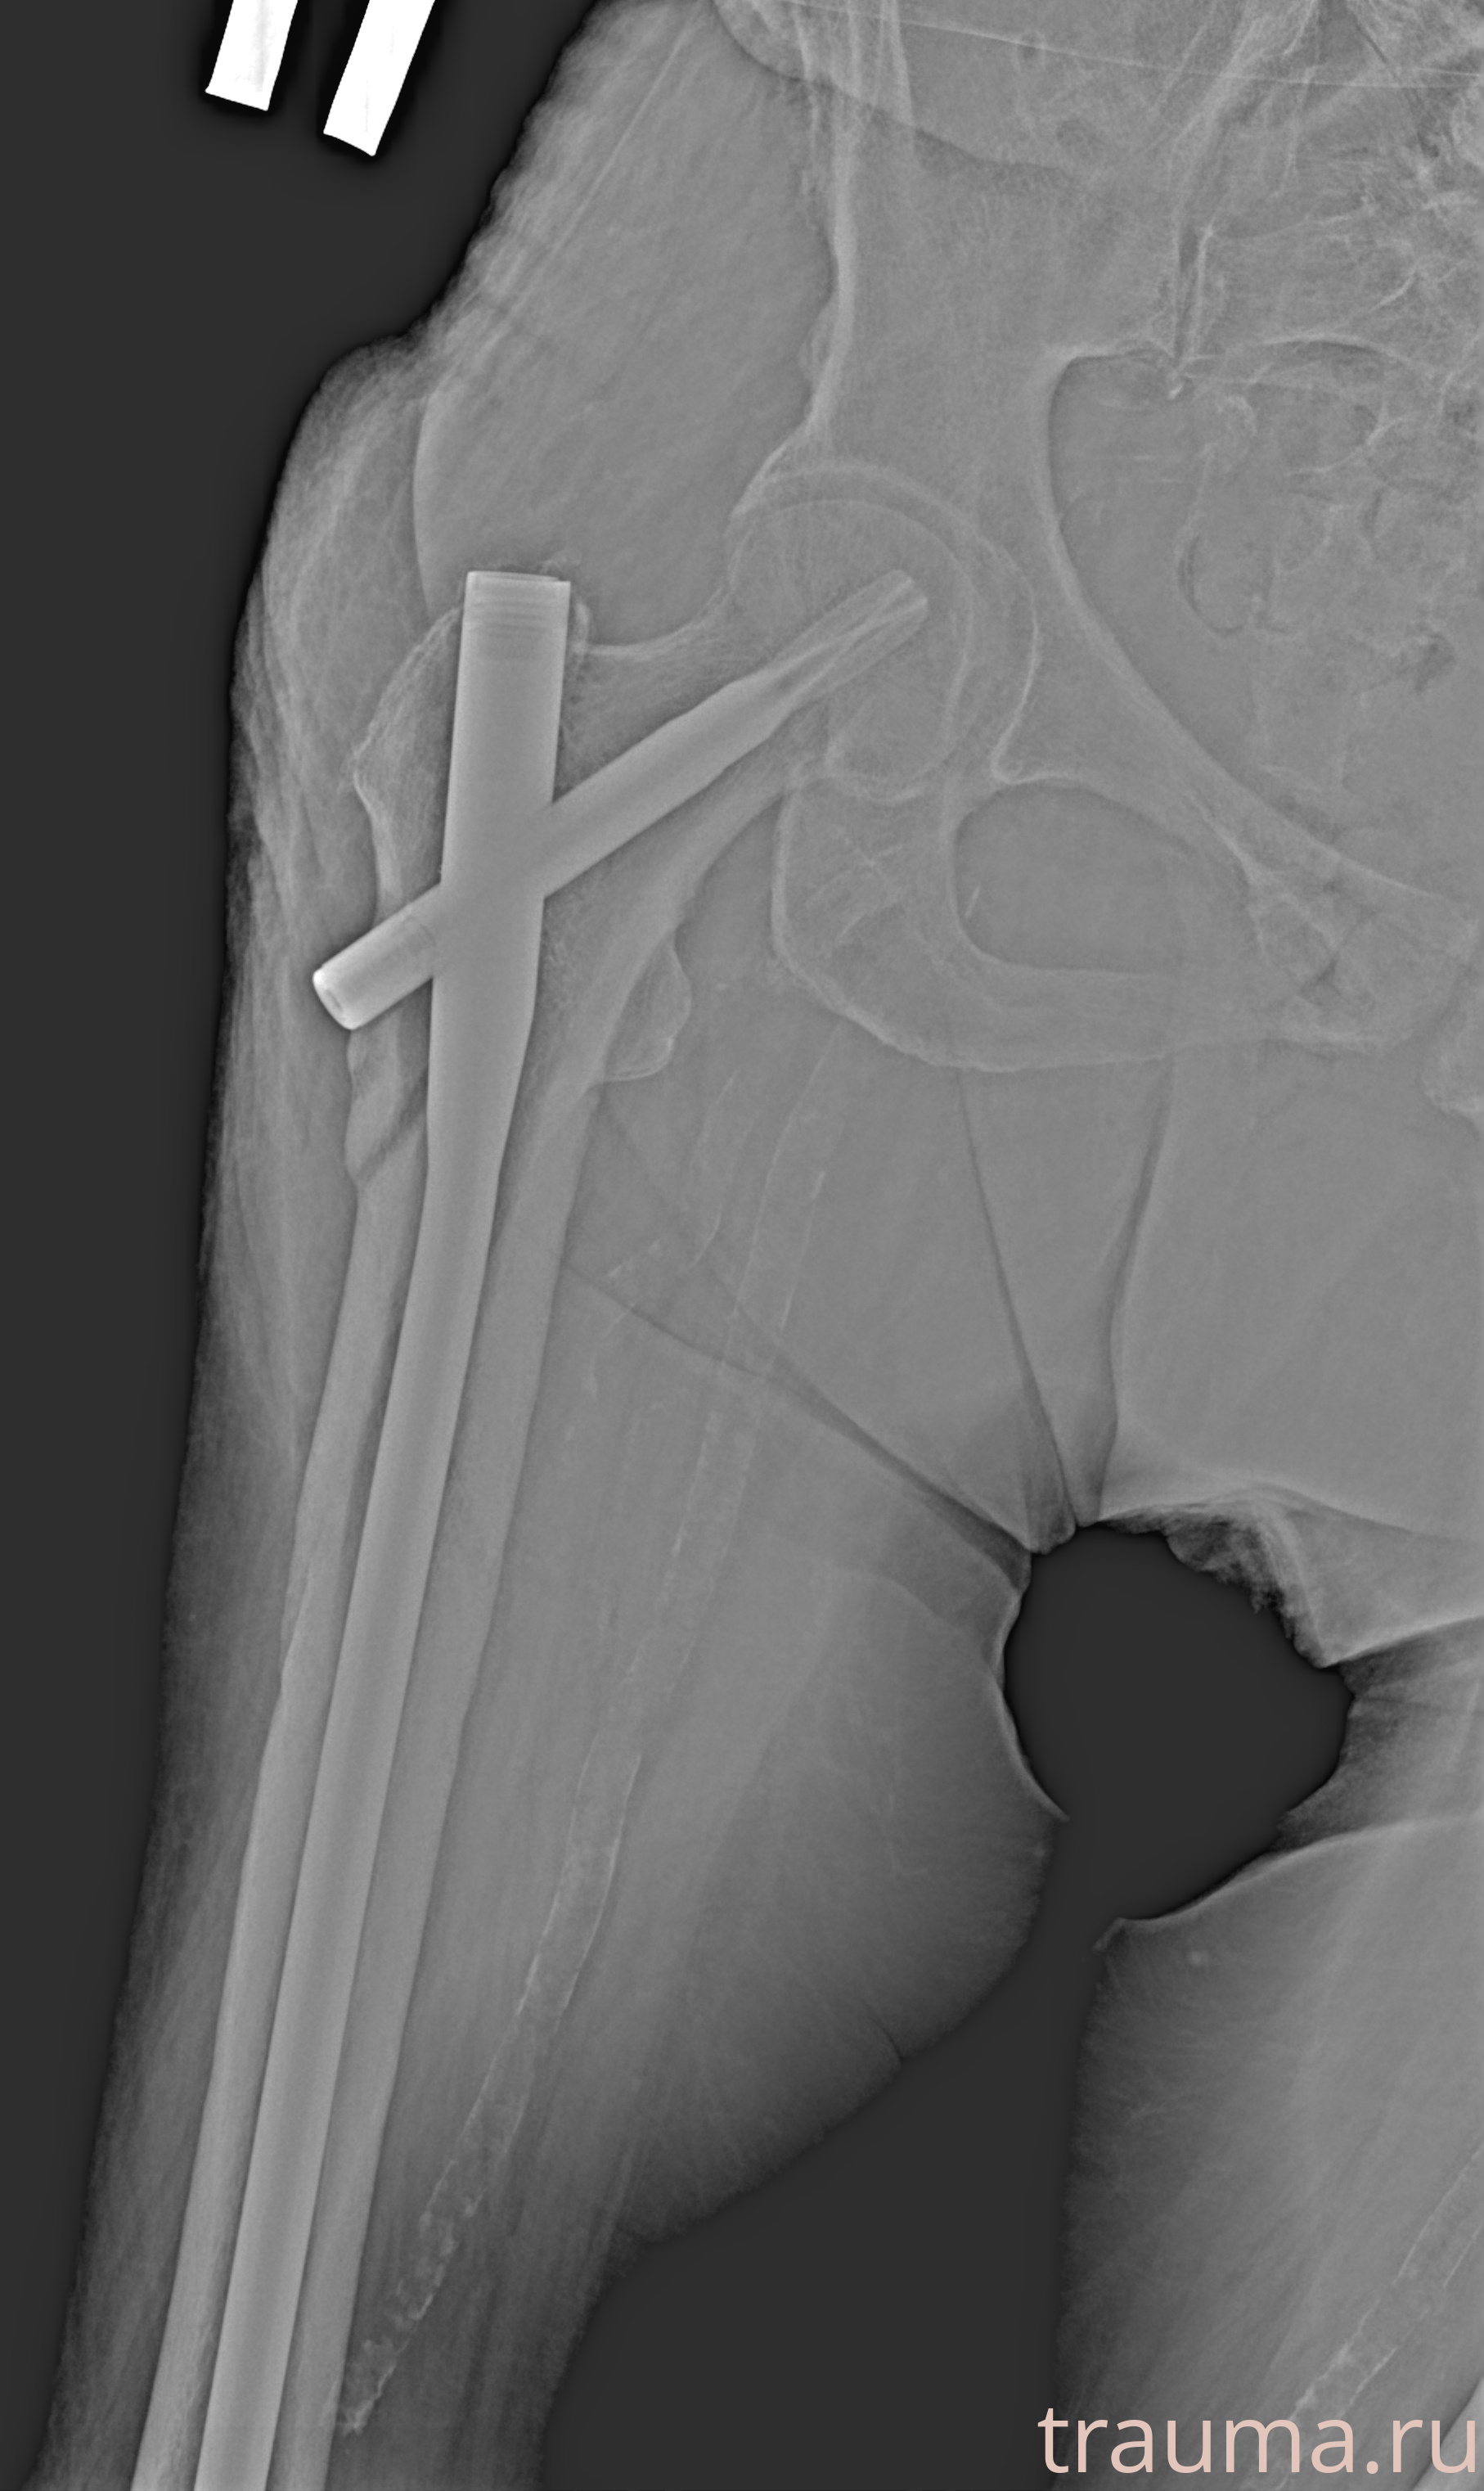

Рентгенограммы